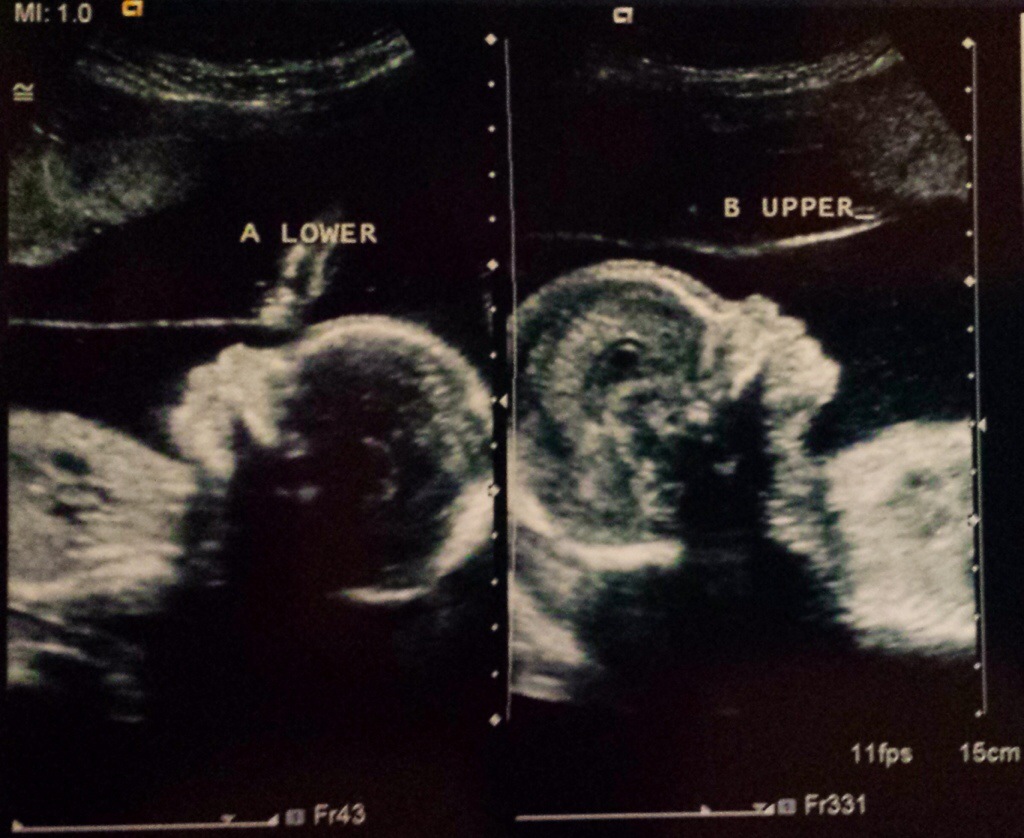

Yesterday was our 20 week ultrasound and we found out we are having 2 girls!!!!

Most of all, the detailed ultrasound reassured us that the girls are doing great. Anatomy looked great and they are measuring normal for their gestational age and almost the same in size. Both were quite active during the scan and it was amazing to see their fingers, toes, noses, lips, etc.

Here are the little ones: